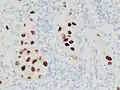

Metastatic melanoma on immunohistochemistry for Melan-A, which helps in diagnosing uncertain cases

Metastatic melanoma on immunohistochemistry for SOX10, another helpful stain in uncertain cases